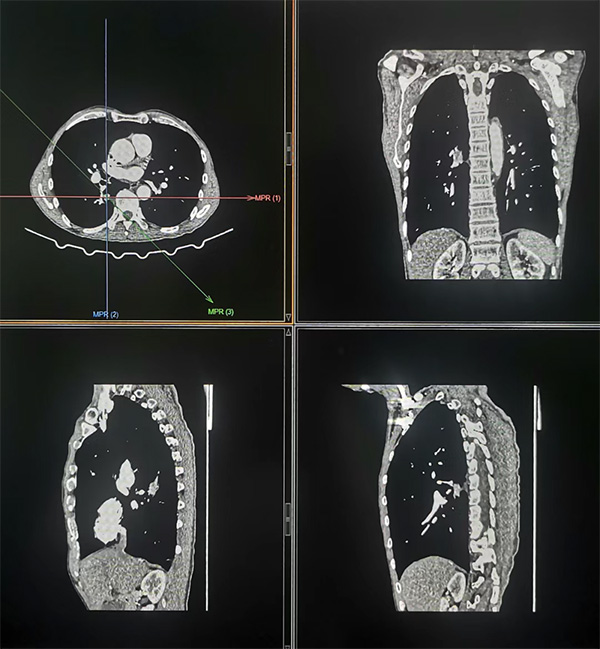

经增强CT检查发现右肺一病灶特殊,可见分叶、毛刺、胸膜凹陷、充气支气管、棘样突起征,同时病灶周围血管丰富。因患者有重度肺气肿,穿刺活检时发生大出血及气胸等并发症的风险极高。因患者及家属已是几经周折,此次非常期望能够明确诊断。经医学影像科团队反复研究病人情况、病灶特点和周围血管关系后,规划了最优穿刺路径,并制定了大出血及气胸等并发症风险应急预案。充分做好应急处置准备的情况下,在团队成员协助下,熊江主任为患者行经皮肺穿刺活检术,成功获取两条灰褐色、鱼肉样活体肺组织标本送病理科检查。手术过程顺利,15分钟时间完成,未发生任何穿刺并发症。